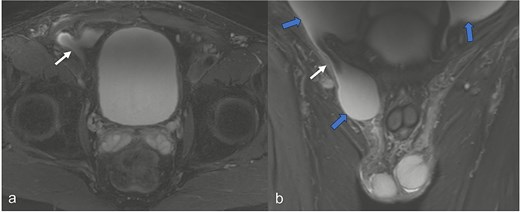

A 52-year-old male patient presented for surgical treatment of a recurrent hernia in the right groin. The preoperative sonography revealed a hernial orifice with a diameter of ~1 cm. In addition, there was clear ascites with a collection of fluid in the spermatic funiculus and a suspected mural tunica vaginalis. A subsequent magnetic resonance imaging (MRI) examination of the pelvis showed a similar picture (Fig. 1). Due to the suspicious appearance of the tunica vaginalis, the recurrent hernia was not repaired at that time. In the renewed physical examination and history taking, the patient reported not only the familiar painful feeling of pressure in the area of the known inguinal hernia but also an increasing feeling of fullness over the entire abdomen. He had also lost 3 kg in weight in the last two months. He had been professionally exposed to asbestos while working as a master electrician in old houses. In the blood count, the C-reactive protein was slightly elevated at 1.88 mg/dl, the thrombocytes at 456 000/μl and the leukocytes at 12 000/μl. The subsequent computed tomography (CT) thorax and abdomen revealed a peritoneal carcinomatosis with ascites without evidence of a primary tumor (Fig. 2). An ascites puncture with subsequent cytological analysis revealed no pathological findings. The subsequent diagnostic laparoscopy revealed a four-quadrant metastasis with nodular structures on the peritoneum (Fig. 3) and the greater omentum. Biopsies taken from the peritoneum and greater omentum revealed a malignant high-grade epithelioid mesothelioma of the peritoneum (Fig. 4). After the tumor conference decision, another laparoscopy was performed to reduce the tumor tissue, after which the affected greater omentum and part of the peritoneum were removed. Hyperthermic intraperitoneal chemotherapy (HIPEC) was then carried out, which was well tolerated and led to a complete remission during the 24-month follow-up period.

Abdominal CT imaging shows clear ascites (blue arrows) in all quadrants in the axial segments (a and b), the coronary segment (c), and sagittal segment (d), and a tumor-specific structure with thickening of the peritoneum and the greater omentum (red arrows). In (c) representation of the hernial orifice (white arrows).